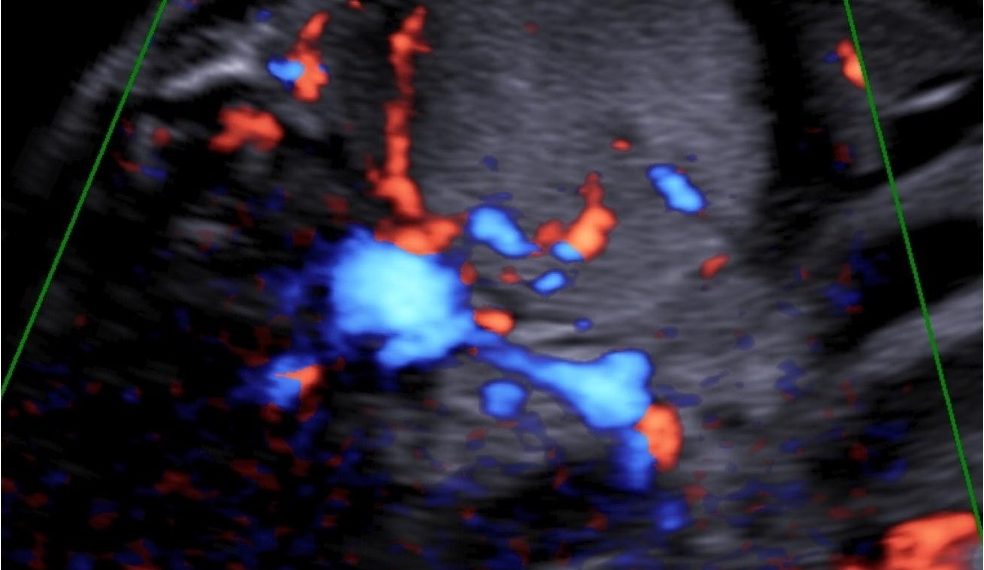

caso clinico SIEOG ost settembre 2022 risposta

caso clinico_settembre 22 risposta